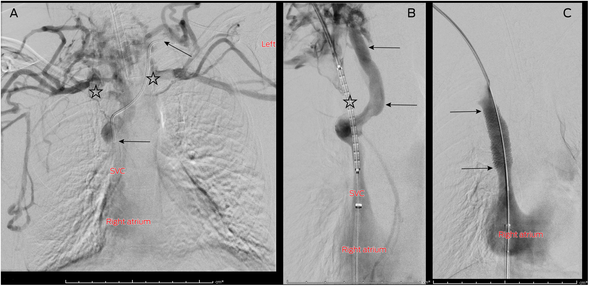

Under general anaesthesia, central venography confirmed CT findings. The retained 15 cm of intravenous catheter was noted in the left BCV and IJV as well as large, well established vertebral and hemiazygos venous collaterals (Box 1, A).1 The retained catheter was removed intact using angioplasty and a snare device via the left neck. To optimise inline blood flow to the SVC, the decision was made to recanalise the right BCV only. This is technically easier than bilateral venous reconstruction, with reduced rate of significant procedural complications but equal SVCS symptom improvement. Covered stenting over the left central venous outflow does not cause contralateral upper limb swelling.2,3 Attempted wire recanalisation of the occluded right BCV from above and below was unsuccessful due to well developed collaterals and chronic fibrous obstruction. A large angioplasty balloon was placed via the right common femoral vein into the SVC. The inflated balloon was used as a target for sharp wire recanalisation from the right neck, re‐establishing continuity with the SVC. An 8 × 59 mm balloon expandable covered stent (off‐label usage; Viabahn VBX, WL Gore and Associates; Supporting Information and Box 1, B) was placed precisely from the patent origin of the right BCV to the patent SVC and dilated to 16 × 42 mm. Sixteen millimetres is an adult SVC diameter, in case of further patient growth, and allows good venous flow, but reduces the risk of intraprocedural venous rupture and pericardial tamponade associated with larger venous stents.3 Completion venography showed rapid inline flow with disappearance of collaterals (Box 1, C). A 6.6 French low profile single lumen TIVAD was inserted via the right IJV, with the line tip at the superior cavoatrial junction.4,5 At the end of the procedure, her anterior chest wall veins were no longer visible and facial plethora had improved. Her SVCS symptoms resolved within 24 hours, and she was discharged home ten days later after a planned cystic fibrosis tune‐up using her new TIVAD. She remains well more than one year after the procedure, with no return of the SVCS symptoms. She remains on warfarin (target INR, 2–3) as a precaution due to the remaining central venous catheter.6 She continues on regular clinical review for cystic fibrosis, with instructions to seek prompt medical advice if she develops any recurrence of the SVCS symptoms.

Box 1 – (A) Central venography performed via bilateral upper limb contrast injection with the patient's arms by her side, showing bilateral brachiocephalic vein (BCV) obstruction (stars).* (B) Recanalised right BCV containing undeployed covered stent (star).† (C) Central venogram after covered stent deployment (arrows) in the right BCV showing rapid inline flow to the right atrium and disappearance of venous collaterals (compare with panels A and B)

* Note the retained left BCV catheter (arrows). † Note the large paraspinal venous collateral bypassing the chronic right BCV occlusion (arrows).